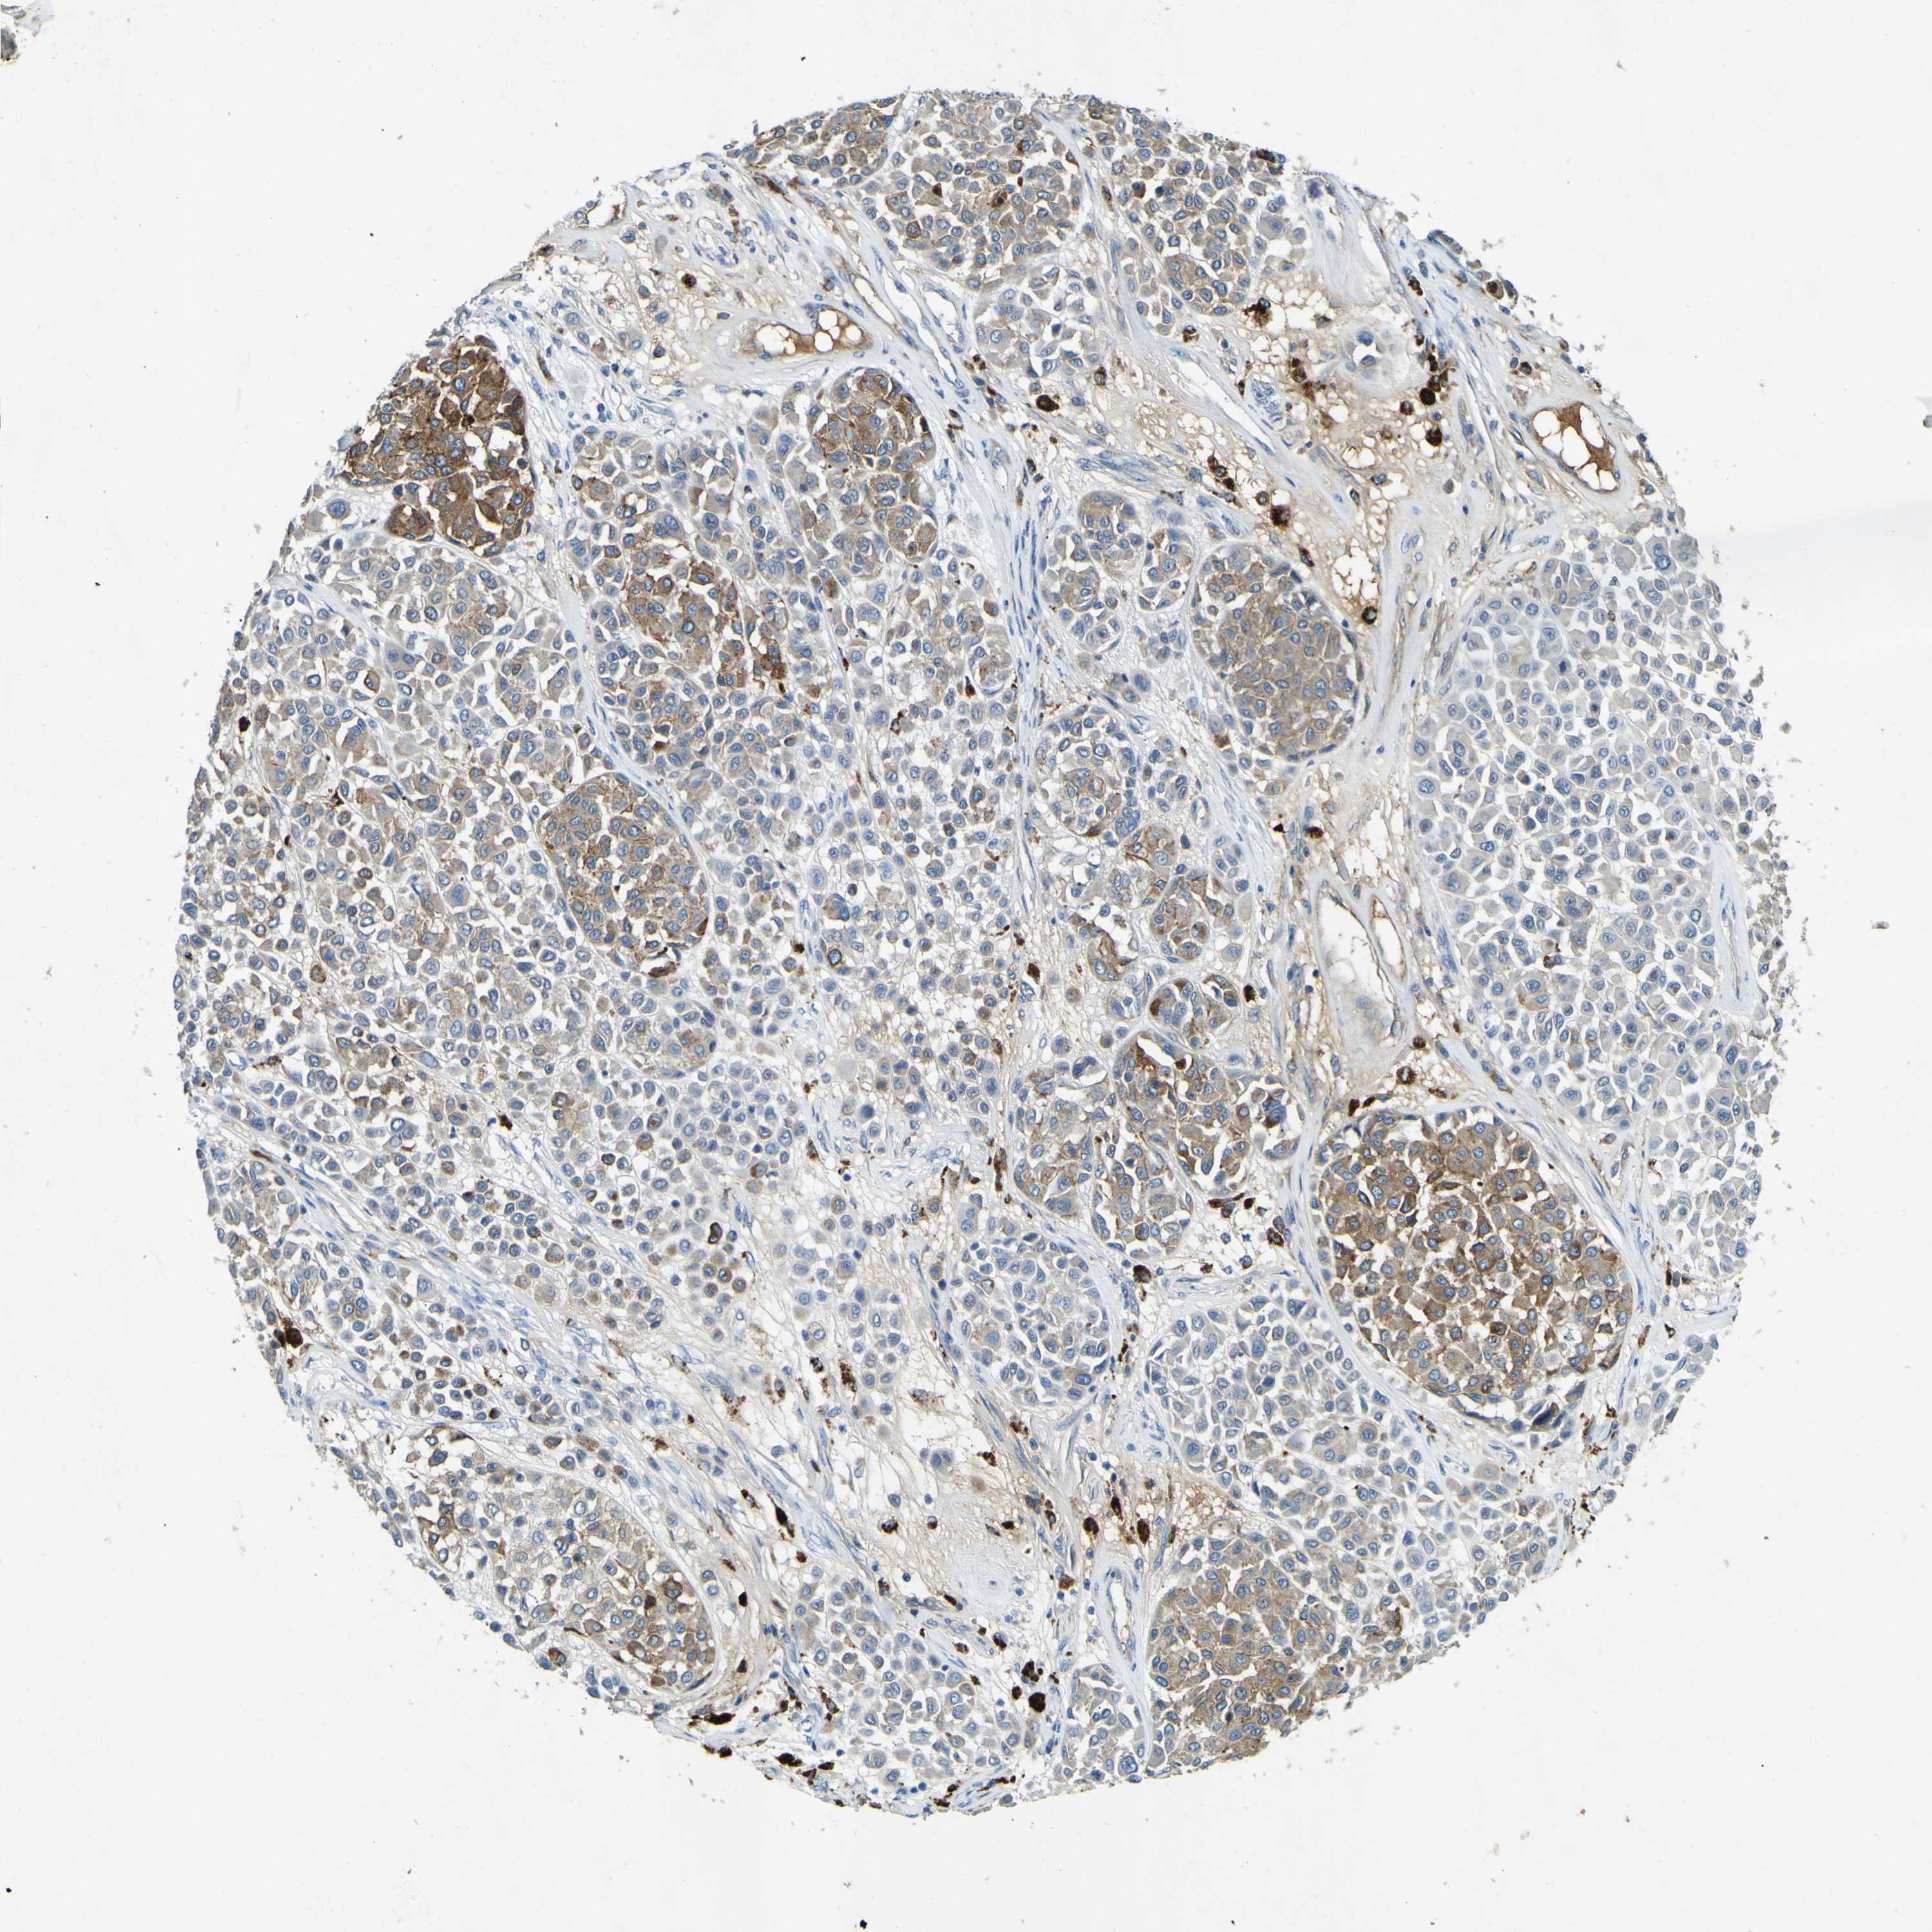

MELANOMA - Protein expressioni

A mouse-over function shows sample information and annotation data. Click on an image to view it in a full screen mode. Samples can be filtered based on level of antibody staining by selecting one or several of the following categories: high, medium, low and not detected. The assay and annotation is described here.

Note that samples used for immunohistochemistry by the Human Protein Atlas do not correspond to samples in the TCGA dataset.

Antibody stainingi

Antibody staining in the annotated cell types in the current human tissue is reported as not detected, low, medium, or high, based on conventional immunohistochemistry profiling in selected tissues. This score is based on the combination of the staining intensity and fraction of stained cells.

Each image is clickable and will lead to virtual microscopy that enables deeper exploration of all samples and also displays staining intensity scores, fraction scores and subcellular localization as well as patient and tissue information for each sample.

Antibody HPA011380

Staining

High

Medium

Low

Not detected

Intensity

Strong

Moderate

Weak

Negative

Quantity

>75%

75%-25%

<25%

None

Location

Nuclear

Cytoplasmic/membranous

Cytoplasmic/membranous,nuclear

Malignant melanoma, NOS

Malignant melanoma, Metastatic site